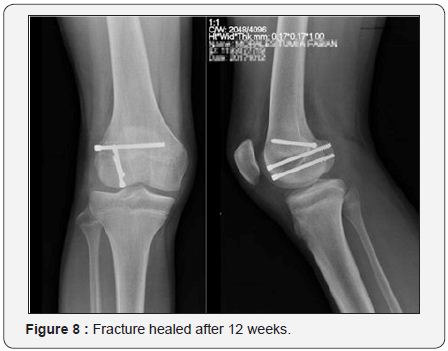

At 12 weeks post operatively both the fracture and the osteotomy had healed (Figure 8) and the patient had complete range of motion and a stable knee (Figure 9).